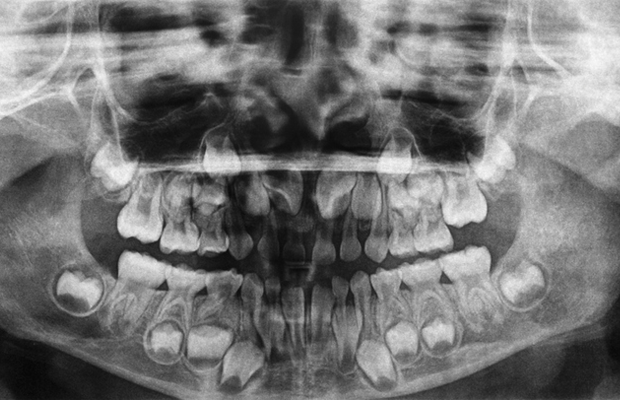

Приблизительно в 6 лет молочные зубы вашего ребенка начинают меняться на взрослые зубы (коренные).

Пока ваш ребенок находится в этом возрасте и начинает терять передние зубы, важно знать, что в задней части рта располагаются взрослые моляры.

Эти зубы проходят через десну без замены молочного зуба и часто остаются незамеченными.

По мере того, как взрослые зубы перемещаются в нужное положение, они вызывают разрушение корней молочных зубов, те ослабевают и выпадают.